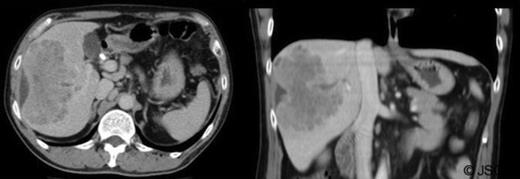

Over the next few months, the man was admitted for repeated cholangitis episodes. ERCP now indicated intra-hepatic duct filling defects (figure 4) and sediment was removed with new stents placed. Repeat abdominal-CT scans indicated the mass was similar in size. Following these presentations, the multidisciplinary team decided to undertake laparoscopic liver biopsy.